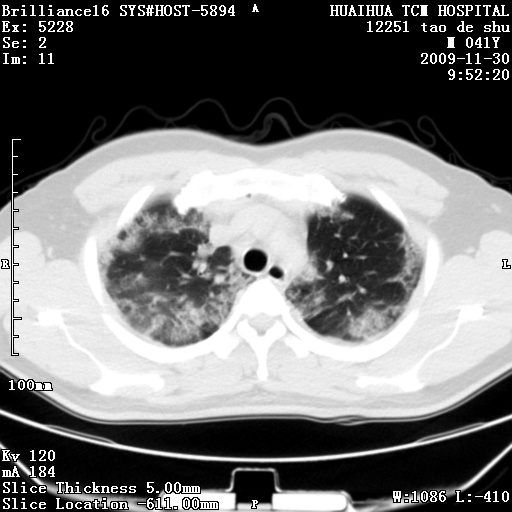

男性,41岁,林业局干部。5天前(2009-11-25)因受寒咳嗽发热在市一医院门诊就诊,胸片报告支管炎。门诊治疗无好转,遂转入我院住院治疗。现主要为发热,38度,咳嗽较轻。血象不高,中性72%,嗜酸性细胞未见报告。血小板8万。尿有蛋白管型。肝功能异常。心电图:阵发性心动过速。请分析ct是什么病。

补充图片:

肺窗图像太少,考虑间质性肺炎

两肺上叶炎性改变,查一下咽拭子培养考虑甲流?

两肺外带斑片状及磨玻璃样高密度灶,考虑感染性病变,过敏性肺炎不除外。

1、双肺感染性病变,查有无重症甲流

2、查过 hiv,不能除外pcp

血下板低,不会是出血合并感染吧,有咯血吗.